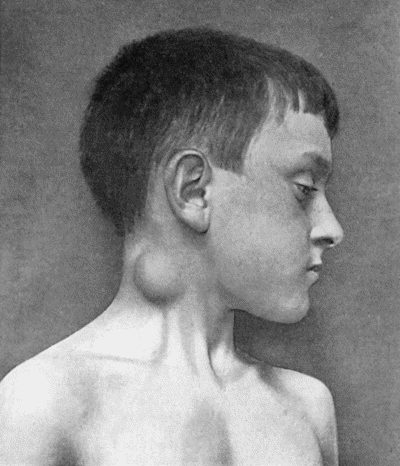

Fig. 1.—Ulcer of back of Hand covered by flap of skin raised from anterior abdominal wall. The lateral edges of the flap are divided after the graft has adhered.

Another modification is to raise the flap but leave it connected at both ends like the piers of a bridge; this method is well suited to defects of skin on the dorsum of the fingers, hand and forearm, the bridge of skin is raised from the abdominal wall and the hand is passed beneath it and securely fixed in position; after an interval of 14 to 21 days, when the flap is assured of its blood supply, the piers of the bridge are divided (Fig. 1). With undermining it is usually easy to bring the edges of the gap in the abdominal wall together, even in children; the skin flap on the dorsum of the hand appears rather thick and prominent—almost like the pad of a boxing-glove—for some time, but the restoration of function in the capacity to flex the fingers is gratifying in the extreme.

Fig. 1.—Ulcer of back of Hand covered by flap of skin raised from anterior abdominal wall. The lateral edges of the flap are divided after the graft has adhered.